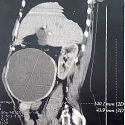

Myosite focale de la cuisse

Zeineb Alaya, Walid Osman

PAMJ. 2017; 26: 200. Published 13 April 2017